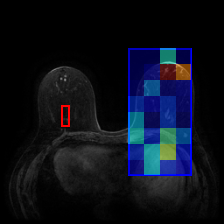

Using the trained models with state-of-the-art performance, we follow the protocol detailed in Section 2.4 and present experimental results on interpretability in Figure 3, Figure 4, and Table 3. In particular, Figure 3 illustrates several qualitative examples, while Table 3 displays pointing game accuracy and mean IoU scores. Finally, Figure 4 represents IoU distributions represented in the form of boxplots. Based on these results, we make the observations below.

Qualitative results can be misleading. In Figure 3, we present qualitative interpretability outputs for all methods considered. As can be seen, depending on the selected subset of images and the method, both accurate and inaccurate interpretability maps can be found. These findings emphasize the danger of making strong claims about interpretability methods based solely on qualitative results, including attention maps.

Pretraining method influences the interpretability outcome. While most models achieve similar accuracies on the same dataset, their interpretability outcomes differ significantly, as seen in Table 3. This indicates that pretraining methods indeed affect interpretability outcomes. Specifically, in the majority of cases (though not all), self-supervised pretrained models yield higher performance with attention maps. However, contrasting the findings reported by [4], we find that interpretability results from DINO may not necessarily outperform those from supervised or MAE pretraining. This suggests that certain pretraining tasks may be more suitable for specific medical datasets than others.

GradCAM interpretability for ViTs is inadequate. In both evaluation types and across multiple models, GradCAM is significantly outperformed by both attention maps and Chefer method, revealing that both methods are more appropriate for ViT interpretability compared to GradCAM, which was originally proposed for CNNs.

Attention maps show promise for interpretability. As shown in Table 3 and Figure 4, interpretability results of attention maps and the Chefer method are comparable. Attention maps generally perform better in the pointing game, while the Chefer method yields better IoU results. These observations hold true for the majority of models across all datasets, with the exception of CP-Child, where the Chefer method outperforms attention maps in the pointing game. Based on these findings, we suggest that researchers employ attention maps when the goal is to identify the most important location in an image. In other scenarios, however, we recommend using the Chefer method. In summary, while attention maps show promise, we find that the Chefer method is a more appropriate choice for interpretability in medical datasets.